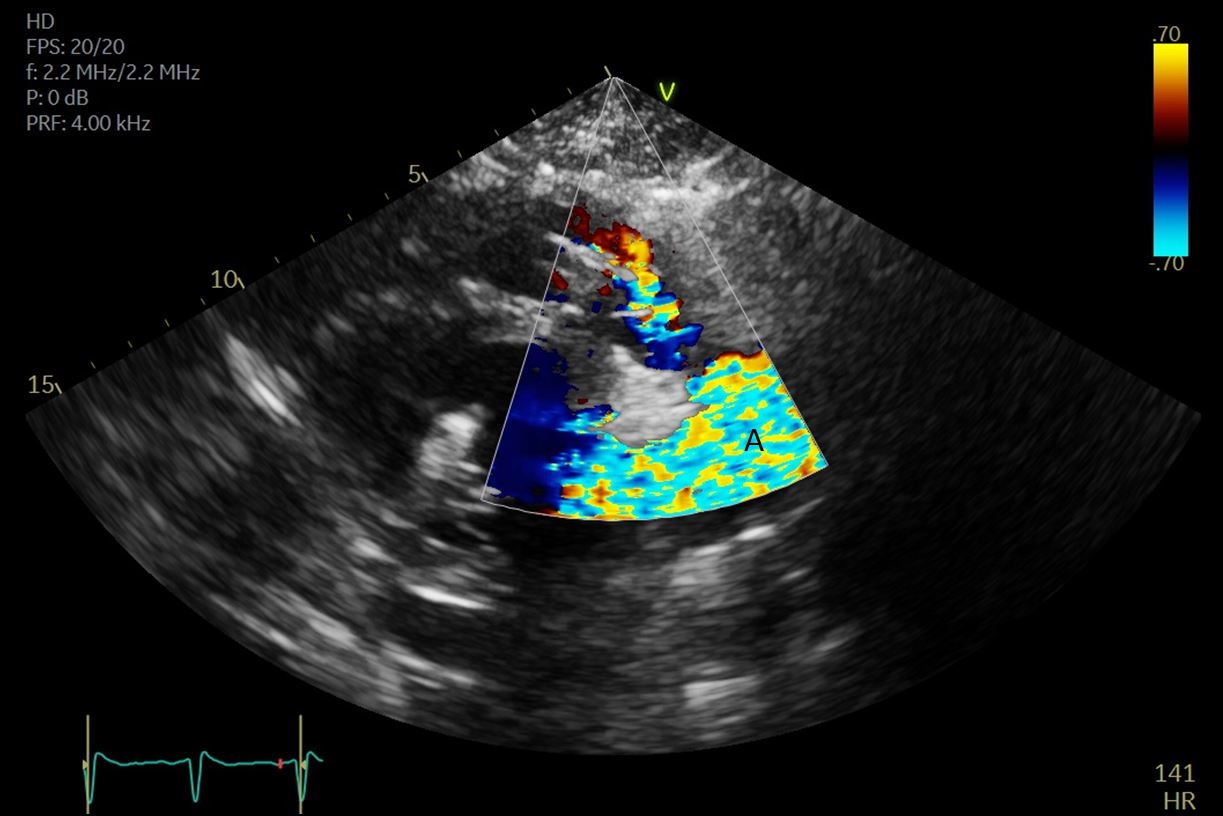

The TandemHeart Protek Duo is a percutaneous right ventricular assist device (RVAD) placed via a dual-lumen 29 French sheath in the right internal jugular vein. The inflow lumen is situated in the right atrium and outflow lumen in the main pulmonary artery. The port lumens are connected externally to a TandemHeart centrifugal pump [31]. As this is generally placed in the operating room, intra-operative TEE can be used to help guide placement. Similar to the Impella RP, bicaval and midesophageal 4 chamber views can visualize the inflow cannula and RV inflow-outflow view and upper esophageal views can be used to visualize the outflow cannula (Figs. 13,14,15). On occasion, its placement can result in distortion of the tricuspid valve morphology with resultant tricuspid regurgitation (Fig. 16). If this is noted, cannula repositioning can be considered. TEE can also help in identifying the ideal pump speed for a patient on TPD support. When utilizing a “ramp protocol”, where the pump speed is progressively increased intraoperatively, midline interventricular septal position can indicate an appropriate amount of RV support [32].

Fig. 14.Color flow imaging demonstrating a mosaic pattern at the inflow port. The interatrial septum and left atrium are also visualized. Note that no blood flow is being entrained from the left atrium across the inter atrial septum. (A) Left atrium. (B) Inflow port in the right atrium. (C) Mosaic pattern at the inflow port on color flow doppler.